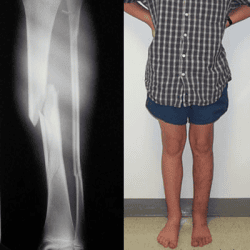

The following patients have allowed us to use images of them to illustrate the miracles that we can accomplish through limb lengthening surgery to fix deformities and injuries in children. For more in depth information on how we treat our pediatric patients, please visit our pediatric case histories page. You can also visit our Conditions Library to learn more about various conditions we treat, their causes and types of available treatments.